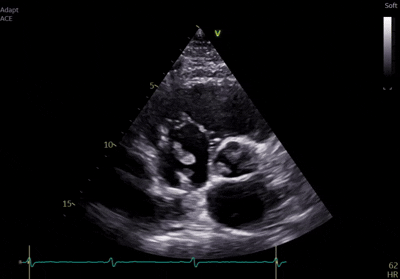

Původně byl hospitalizován na interním oddělení spádové nemocnice pro septický stav nejasné etiologie, kde v hemokulturách opakovaně zachytili Staphylococcus aureus. V rámci pátrání po zdroji infekce byla provedena jícnová echokardiografie (TEE), která odhalila vegetace na stimulačních elektrodách. Po zahájení cílené antibiotické terapie byl pacient přeložen na naše pracoviště k extrakci stimulačního systému.

Kontrolní TEE na našem pracovišti potvrdila vlající vegetace v pravostranných srdečních oddílech – největší o velikosti 25×9 mm, menší přisedlý útvar s rozměrem 7×9 mm. Provedené PET/CT bylo v korelaci se suspektními zánětlivými změnami téměř v celé délce elektrod. V rámci multidisciplinárního týmu bylo vzhledem k velikosti vegetací a rizikovým faktorům rozhodnuto o kardiochirurgické extrakci stimulačního sysému. Transvenózní extrakce představovala větší riziko s nejasným výsledkem - možné embolizace do plic, mechanické komplikace s ohledem na stáří elektrod a známý uzávěr levé v. subclavia. Předoperační přípravu zkomplikovala hluboká žilní trombóza vlevo, která vedla k odkladu výkonu. Začátkem srpna pacient podstoupil kardiochirurgickou extrakci celého systému. Vlastní výkon i pooperační průběh byl bez komplikací a pacient byl přeložen zpět do spádové nemocnice k pokračování antibiotické léčby.